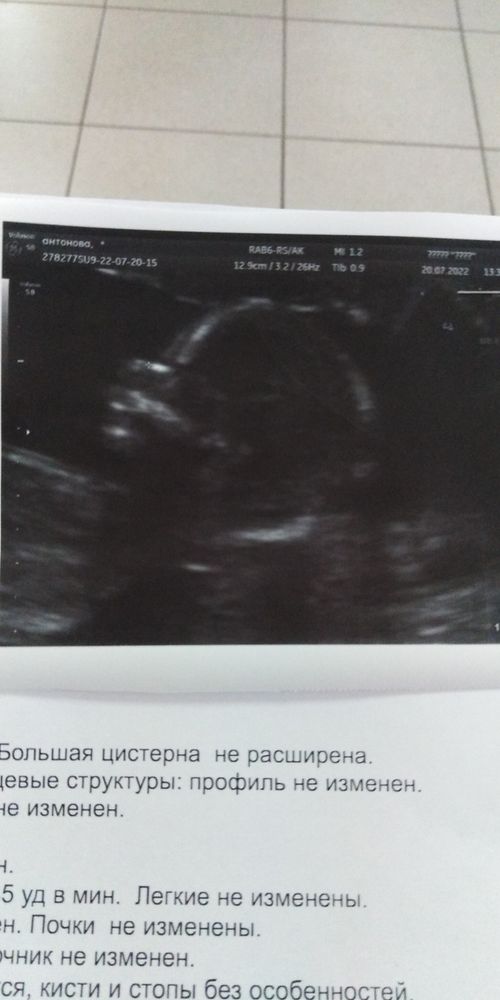

Ну вот и началась 16 неделя. Скрининг позади, комиссия почти пройдена, по результатам скрининга есть риск задержки роста, прописали кардиомагнил 150мг. Девочки кто принимал? Как то страшно начинать пить.